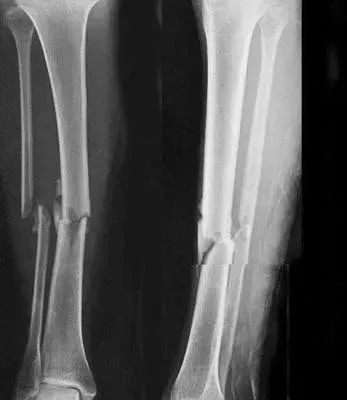

5、小腿踢球時(shí)骨折過,還能當(dāng)兵嗎?

四肢單純性骨折,治愈1年后,X線片顯示骨折線消失,復(fù)位良好,無功能障礙及后遺癥(空降兵除外),合格。